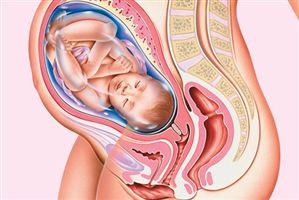

Развитие плода на 42 неделе беременности

Ребенок полностью готов к своему появлению на свет. В материнской утробе ему стало тесно и неудобно. Скелет малыша начинает укрепляться, что может вызвать сложности во время родов, так как родовые пути матери могут получить повреждения.

Большинство новорожденных (95%) на данном этапе появляются на свет совершенно здоровыми.

Плацента продолжает стареть и уже не так эффективно выполняет свои функции. Это значительно увеличивает риск гипоксии у плода.

Ногти у малыша заметно подросли, и после рождения их необходимо будет обрезать, чтобы он не поцарапал себя. Смазка, которая покрывала кожу плода, исчезает, и под воздействием воды на коже могут появляться морщинки.

На этом этапе возможно попадание первородного кала (мекония) в околоплодные воды, что увеличивает риск их инфицирования.

Фото плода на 42 неделе беременности (возраст плода 40 недель)